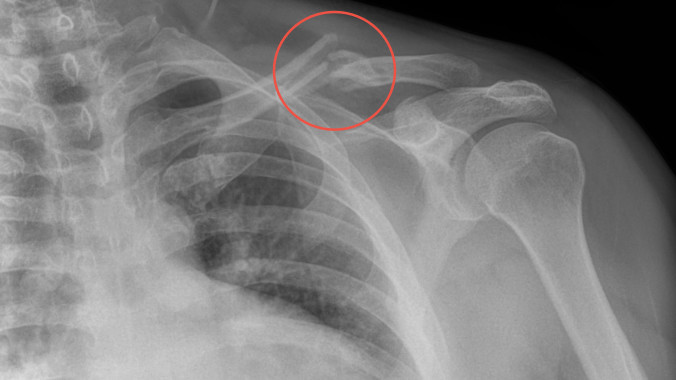

Herramienta de diagnóstico ideal por su portabilidad, recomendada para seguimiento de fracturas, o procedimientos quirúrgicos con implantes, pacientes geriatras con incapacidad para trasladarse a un hospital para evaluación radiográfica.

Ideal para pacientes con incapacidad para trasladarse al hospital o moverse. Fracturados, con fijación externa, osteoporosis, niños, adultos, pacientes geriatras, seguimiento post cirugía ortopédica.